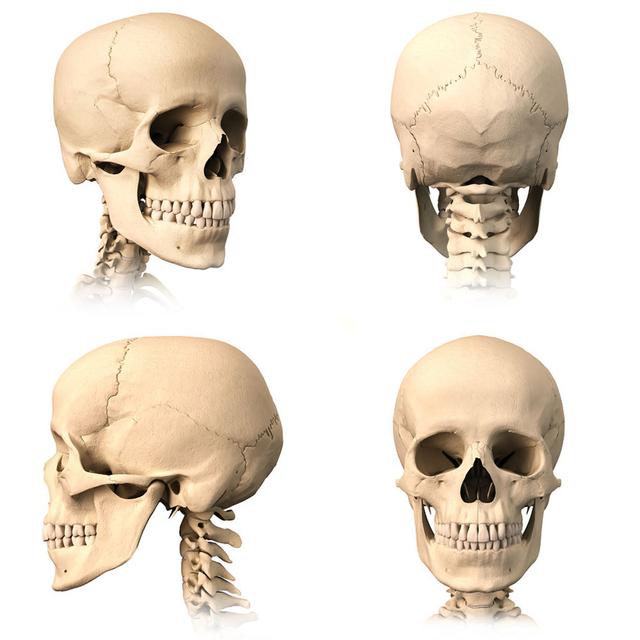

从一方面来说,人类是弱小的,容易生病,容易受伤,但从另一方面来说,人类也是强大的...